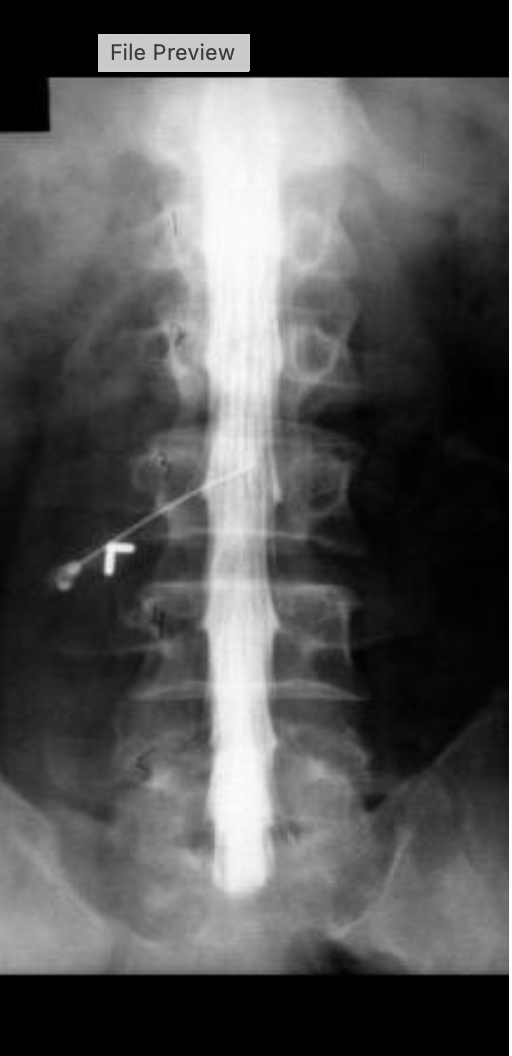

what procedure is being performed on this image

lumbar myelogram

what level is the needle placed at for this procedure

L2/L3

what contrast was used for this procedure

isovue M 200